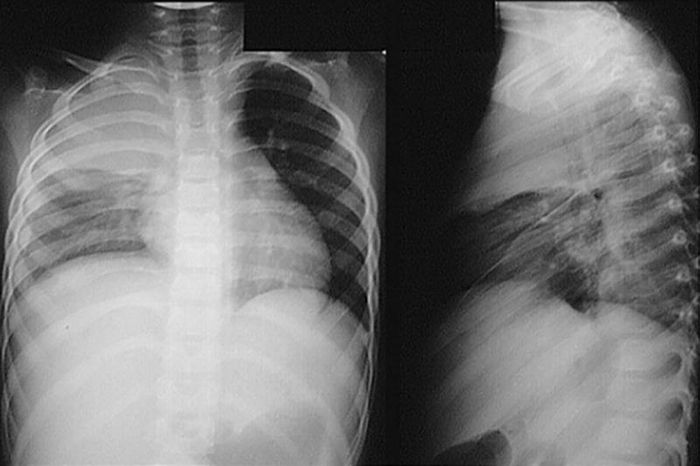

- Chụp X-Quang phổi: Giúp đánh giá tình trạng và chức năng của phổi. Phương pháp này ít hiệu quả trong chẩn đoán các bệnh phổi mạn tính như khí phế thủng hay xơ nang, nhưng rất quan trọng trong việc phát hiện các bệnh nghiêm trọng như ung thư hoặc lao phổi. Ngoài ra, X-Quang còn có thể phát hiện những bất thường phổi do các vấn đề tim mạch, chẳng hạn khi chất lỏng tích tụ trong phổi là dấu hiệu của suy tim sung huyết.

Hình ảnh sẽ càng tối nếu có nhiều tia X chiếu đến phim, những bộ phận cản tia X mạnh như xương sẽ hiện màu trắng, còn những vùng chứa khí như phổi sẽ tối màu. Các mô mềm như cơ hoặc các cơ quan đặc sẽ có màu xám, độ xám tùy thuộc vào mật độ mô. Dựa trên những hình ảnh này, bác sĩ sẽ đọc phim, chẩn đoán và đưa ra phương án điều trị phù hợp.